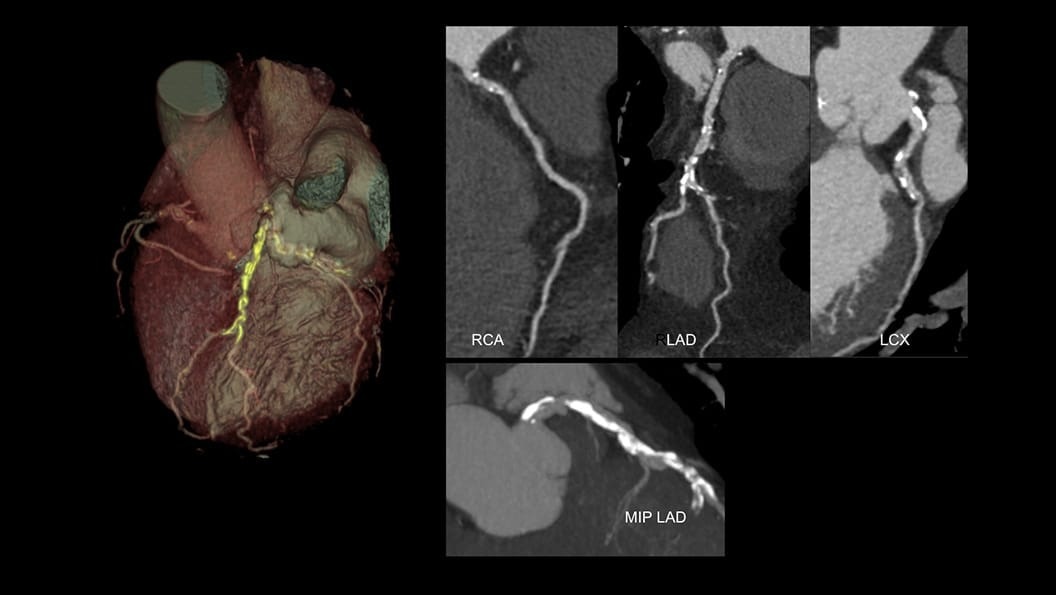

Expect exceptional results routinely—in a single beat

Complex CCTA becomes routine when advanced AI supports every image—streamlining and standardizing workflows even for challenging patients with unreliable ECG traces. See how Radiomed transformed its cardiac CT program to consistently deliver exceptional results.

CardiQ Suite

An integrated suite of CT Cardiac post-processing tools, built for automation and workflow efficiency.

Consistency

>90% concordance with CACS‑DRS classification grouping⁵

Identification

>95% correct identification of the presence of coronary artery calcifications⁵

Labeling

>90% accurately labeled coronary artery territories⁵